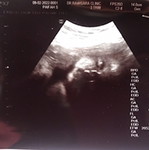

อาทิตย์หน้ามีนัดเร่งคลอด

อาทิตย์หน้ามีนัดเร่งคลอดอยากถามแม่ๆว่าเขาให้นอนโรงบาลไหม แล้วปกติเร่งคลอดแล้วได้คลอดเลยไหมหรือต้องใช้เวลากี่วันค่ะ จะ40วีคแล้วยังไม่มีอาการอะไรเลย พยาบาลไม่ได้แจ้งอะไรให้ใบนัดแล้วก็ให้กลับ #ขอบคุณสำหรับคำตอบค่ะ #คุณแม่ๆช่วยแนะนำหน่อยค่ะ